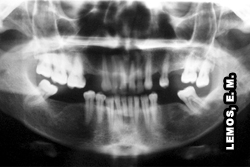

Observar radiografia panorâmica evidenciando tratamento endodôntico em todos os dentes, imagem original extraída de: Cohen, S. & Hargreaves, K. M. Caminhos da Polpa 9a. Ed. Mosby, Elsevier 2007, p59. |

O diagnóstico pode ser representado por uma corrente, na falta de um elo, a corrente será rompida, colocando em risco o sucesso do tratamento | Radiografia panorâmica evidenciando tratamento endodôntico em todos os dentes, qual seria o dente causal? |